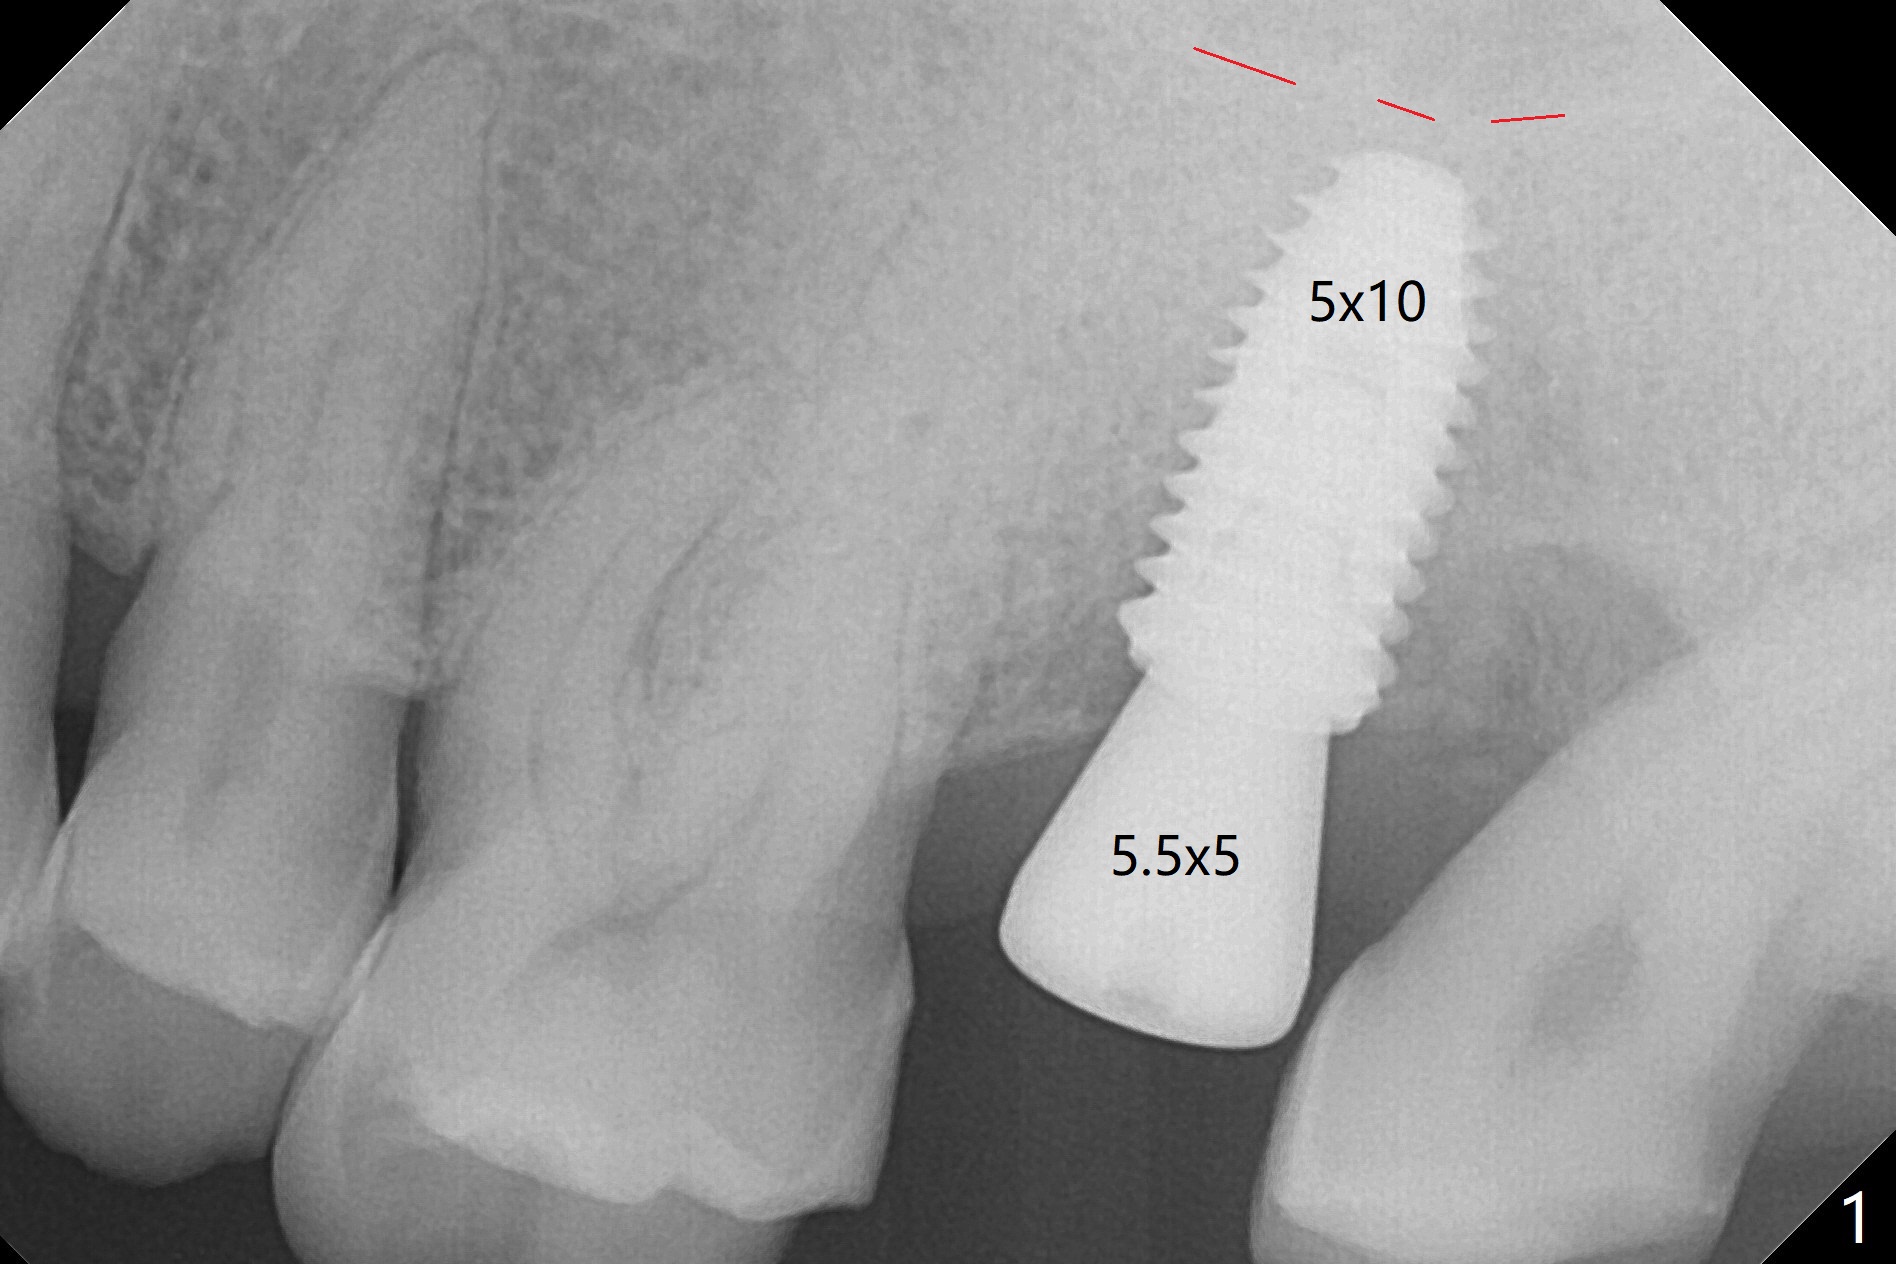

Osteotomy is conducted at #15 according to drill sequence (including the depth of the last drill (no tapping)), but the 5x10 mm implant is placed ~ 1mm shy of the planned depth (Fig.1 (red line: sinus floor)). Clinically the implant is ~ 2 and 4 mm subgingival buccal and palatal, respectively. Bitewing shows the implant being subcrestal mesial and equicrestal distal (Fig.2). If the implant has to be placed deeper, can a 4.0x13 mm drill be used?

Due to the fact that there's additional tip end of 1.2mm at every osteotomy drills, I intentionally put 1 size shorter drilling sequence in order not to perforate sinus membrane. However, if you think that due to the inferior cortical bone, the apex of implant got stuck then you can just go with regular drilling sequence. Not with the 1 size shorter drilling sequence. And then place implant according to the marker of the fixture driver. Jennifer.